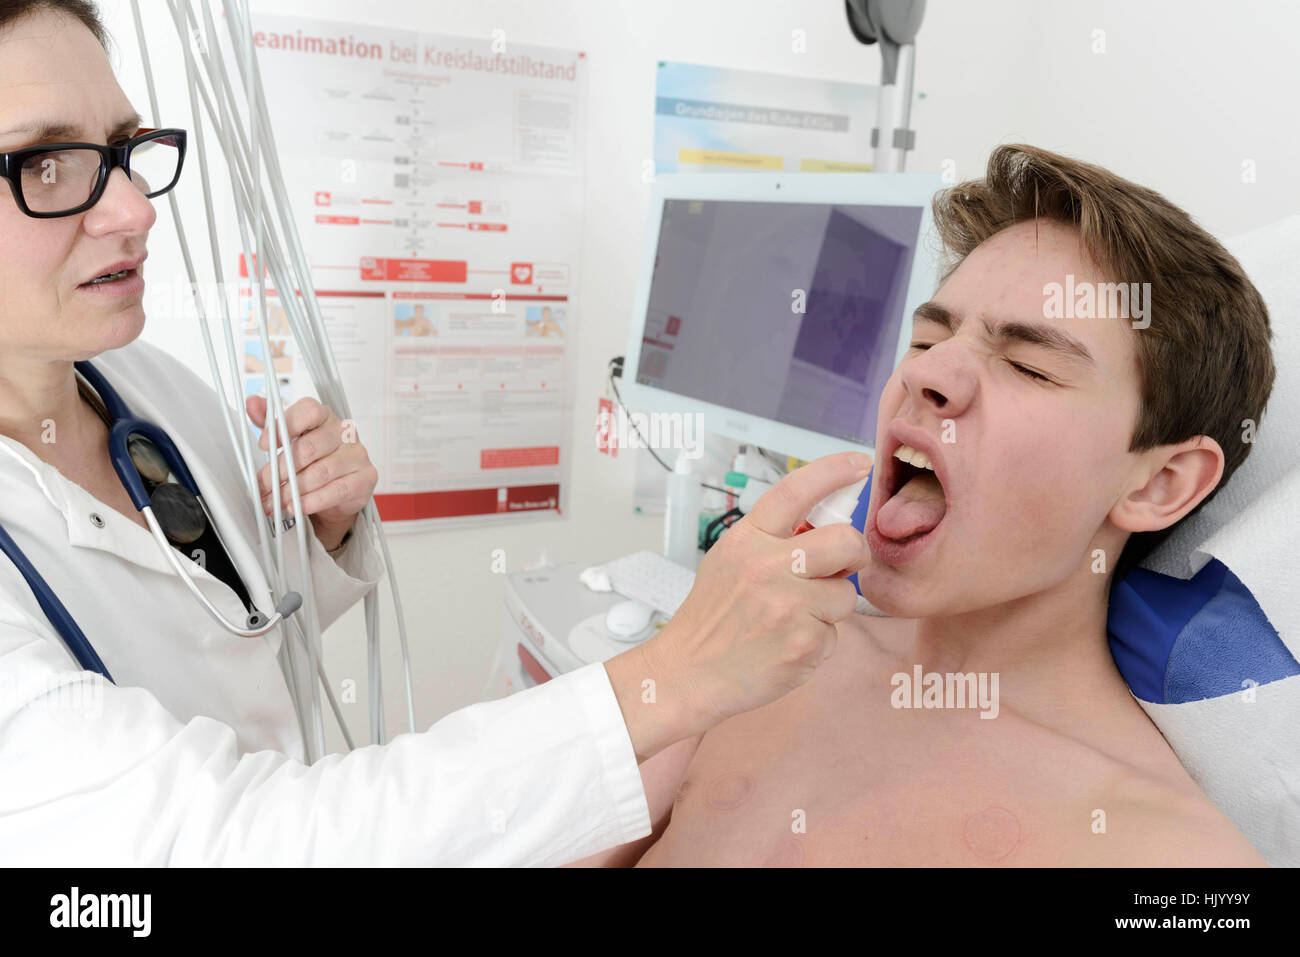

Arzt Sprays orale Desinfektionsmittel Stockfotohttps://www.alamy.de/image-license-details/?v=1https://www.alamy.de/stockfoto-arzt-sprays-orale-desinfektionsmittel-132150535.html

Arzt Sprays orale Desinfektionsmittel Stockfotohttps://www.alamy.de/image-license-details/?v=1https://www.alamy.de/stockfoto-arzt-sprays-orale-desinfektionsmittel-132150535.htmlRMHJYY9Y–Arzt Sprays orale Desinfektionsmittel